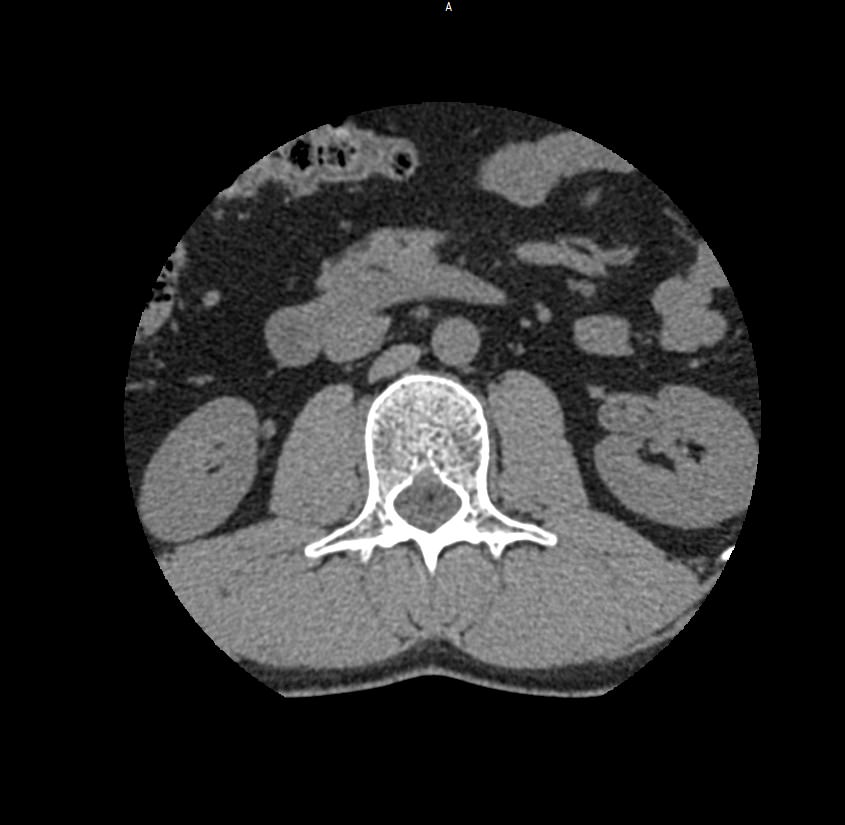

Мультиспиральная компьютерная томография является наиболее точным и информативным методом диагностики различных заболеваний позвоночника и, в частности, пояснично-крестцового отдела. Сканирование проводится при помощи рентгеновского излучения, в результате чего получают серию послойных изображений пояснично-крестцового отдела позвоночника.

В медицинских центрах «Доступная медицина» обследование пояснично-крестцового отдела позвоночника осуществляется на современных мультиспиральных компьютерных томографах последнего поколения TOSHIBA AQUILION в модификациях, позволяющих выполнять одномоментно 64 и 128 срезов анатомической зоны для получения снимков высокого разрешения. Послойное сканирование исследуемой области проводится с минимальной толщиной среза от 0,5 мм, что обеспечивает получение изображений органов в мельчайших подробностях.

Инновационные компьютерные приложения позволяют построить 3D-модель исследуемого органа, обеспечивая детальную визуализацию строения внутренних структур позвонков, хрящевых элементов, кровеносных сосудов и окружающих тканей.

- нет ли грыж (протрузий, экструзий), и если есть – где они находятся, на сколько миллиметров выступают в просвет позвоночного канала, какие анатомические структуры сдавливают;

- состояние паравертебральных мягких тканей (возле позвоночника).